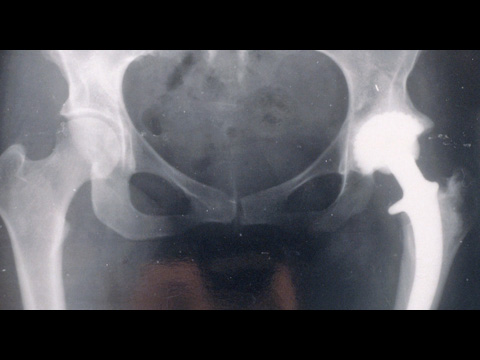

Implants du futur

Mots clés : biomatériaux, implants, polymères, bio-intégration, implant osseux biodégradable, rejets, régénération tissulaire

Trois exemples de recherche sur les biomatériaux et implants de demain :

- polymères pour la bio-intégration des implants et éviter les rejets ;

- implant osseux biodégradable renforçant l’os dans le cas d’ostéoporose et libérant un médicament ;

- mise au point de matériaux biodégradables pour servir de tuteurs à la régénération tissulaire.